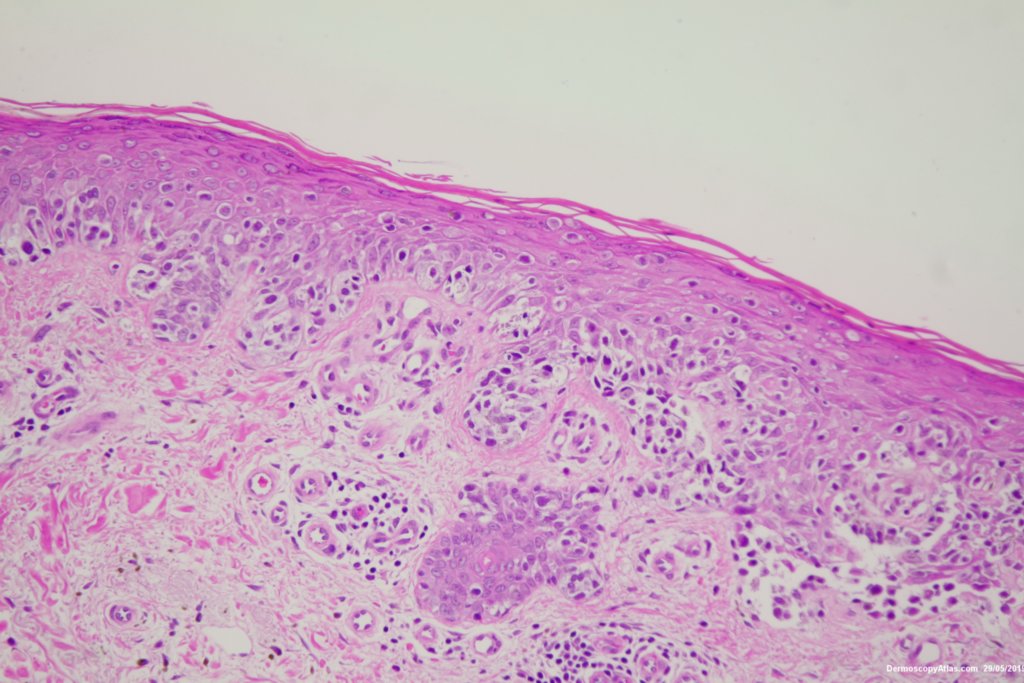

Image Number #3479 (Melanoma invasive)

Diagnosis: Melanoma invasive

Pigmented lesion on the lower leg noted at an annual skin check. The clinical is suggestive of a melanoma but the dermatoscopy was initially interpreted as coiled vessels with lines radial peripheral of an IEC. In IEC the lines radial are usually made up of dots but these are solid streaks. There is some vessel variability in the pink area.

This was an invasive melanoma 0.4 mm thick but the histology shown shows mainly in situ melanoma.Have a look at the second case in the video below for a more detailed overview of the histology.